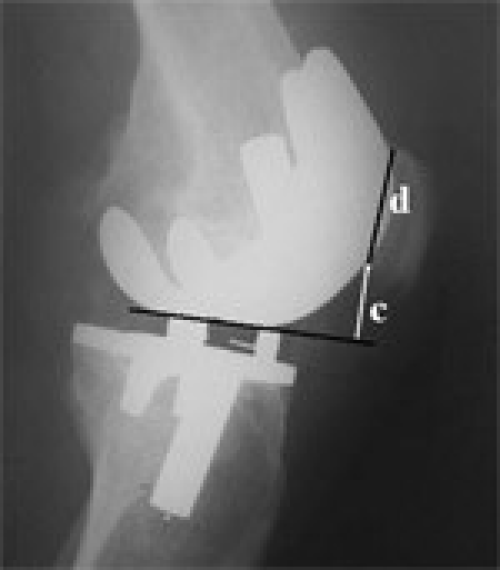

Pseudo-Patella Baja after total knee arthroplasty

Seyyed Morteza Kazemi, Laleh Daftari Besheli

DOI: 10.12659/MSM.881770

Med Sci Monit 2011; 17(5): CR292-296

Seyyed Morteza Kazemi, Laleh Daftari Besheli, Alireza Eajazi, Mohammad Reza Miniator Sajadi, Mohammad Ali Okhovatpoor, Ramin Farhang Zanganeh, Reza Minaei